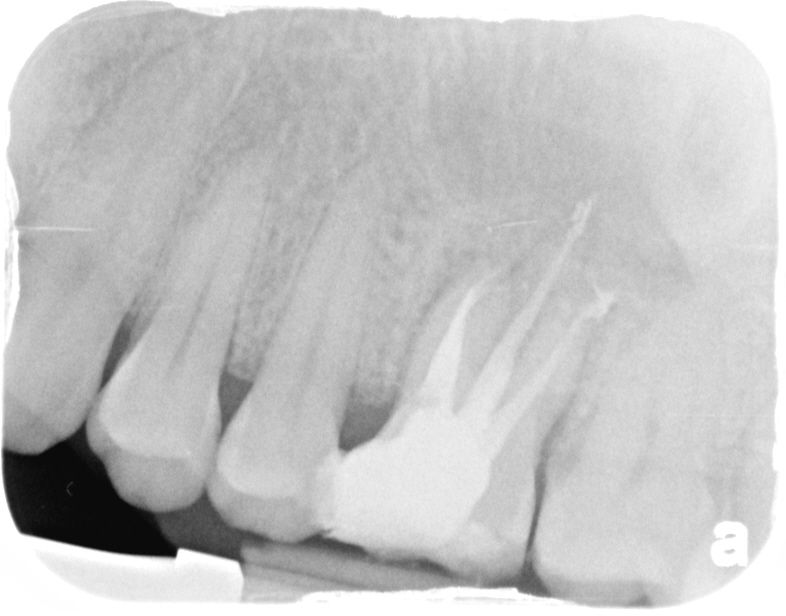

This was a tough one. Anatomy was a 2-1-2. Could not maintain either apical patency, in fact never got the MB1. Can see two apical portals of exit. I removed the isthmus making this a 1-2 with a very deep split. This is CaOH if blow up PA can see split in last 1-2mm. Completed in Mendota.